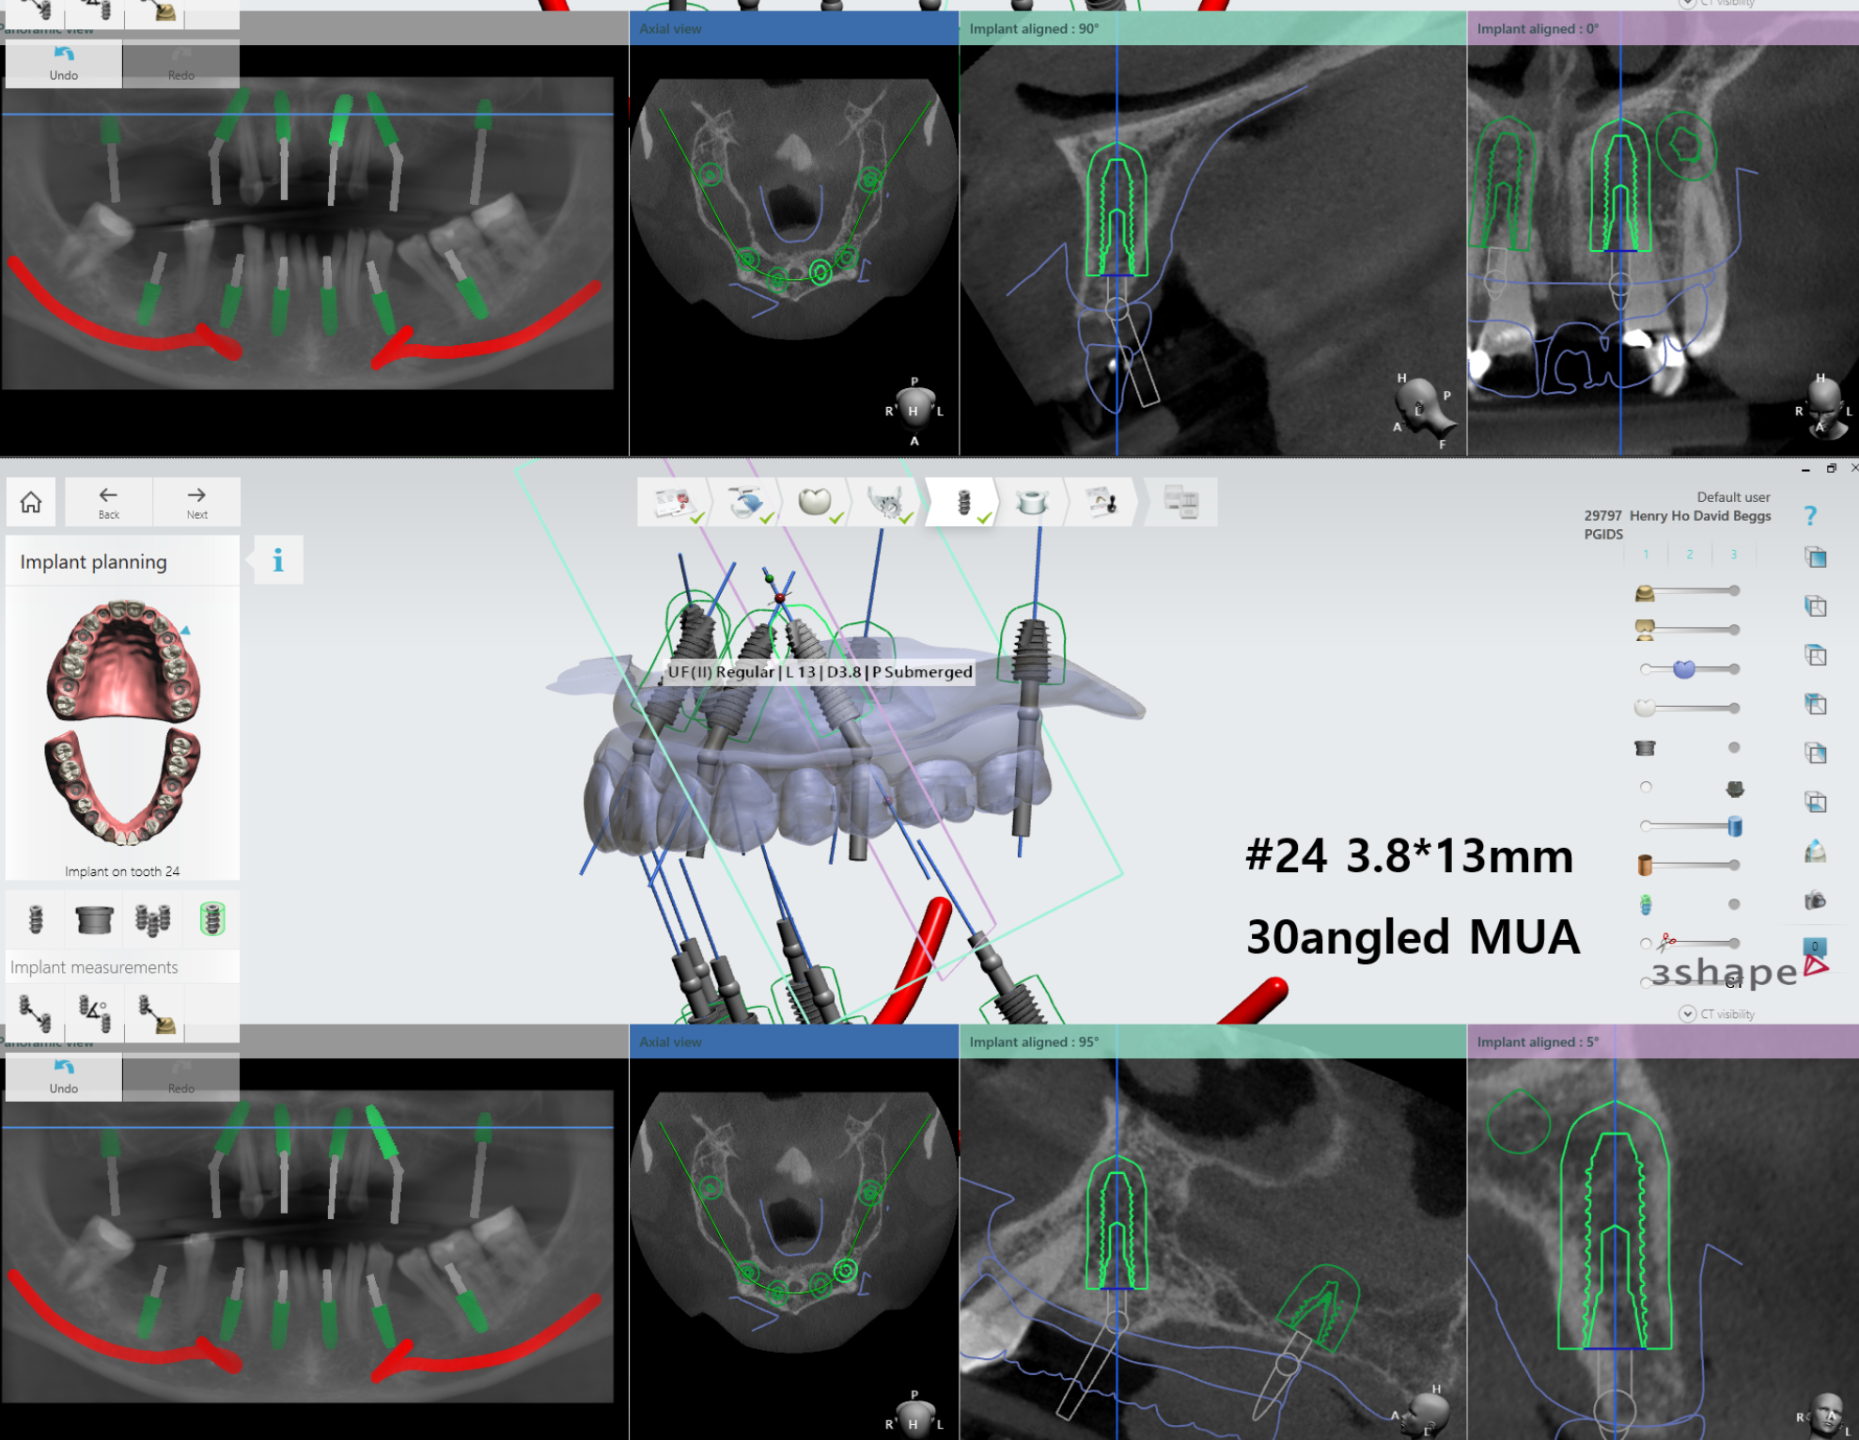

An Introduction to Full Arch Implantology

- Guided Surgery

- Digital workflows

- Digital scanning of teeth, implants and tissues